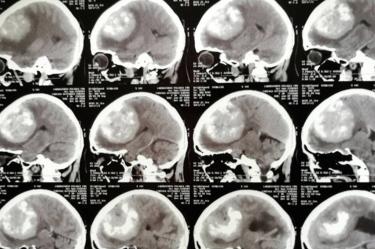

Imágenes por resonancia magnética (RMN).

Tomografía computarizada (TAC).